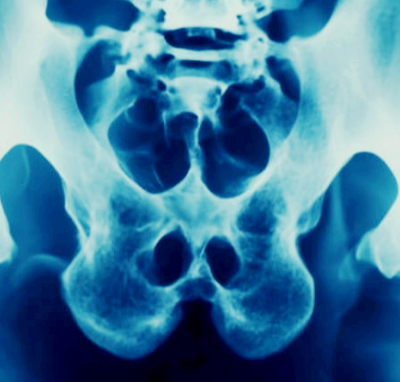

엉치뼈가 아픈이유 통증 원인

엉치뼈가 아픈이유 통증 원인 엉치뼈가 아픈 이유는 생각보다 다양하고 복합적입니다. 단순히 ‘앉아서 오래 있었더니 아프다’고 넘기기엔, 그 속에는 허리, 골반, 신경, 내과적 질환, 심지어는 종양성 질환까지 숨어 있을 수 있습니다. 반복되는 통증이 있다면 자가 진단만으로 해결하지 말고, 꼭 전문 진료를 통해 정확한 원인을 파악하세요. 평소 생활 습관 개선과 운동만으로도 많은 문제를 예방할 수 있으니, 지금 이 순간부터 실천해보시기 바랍니다.